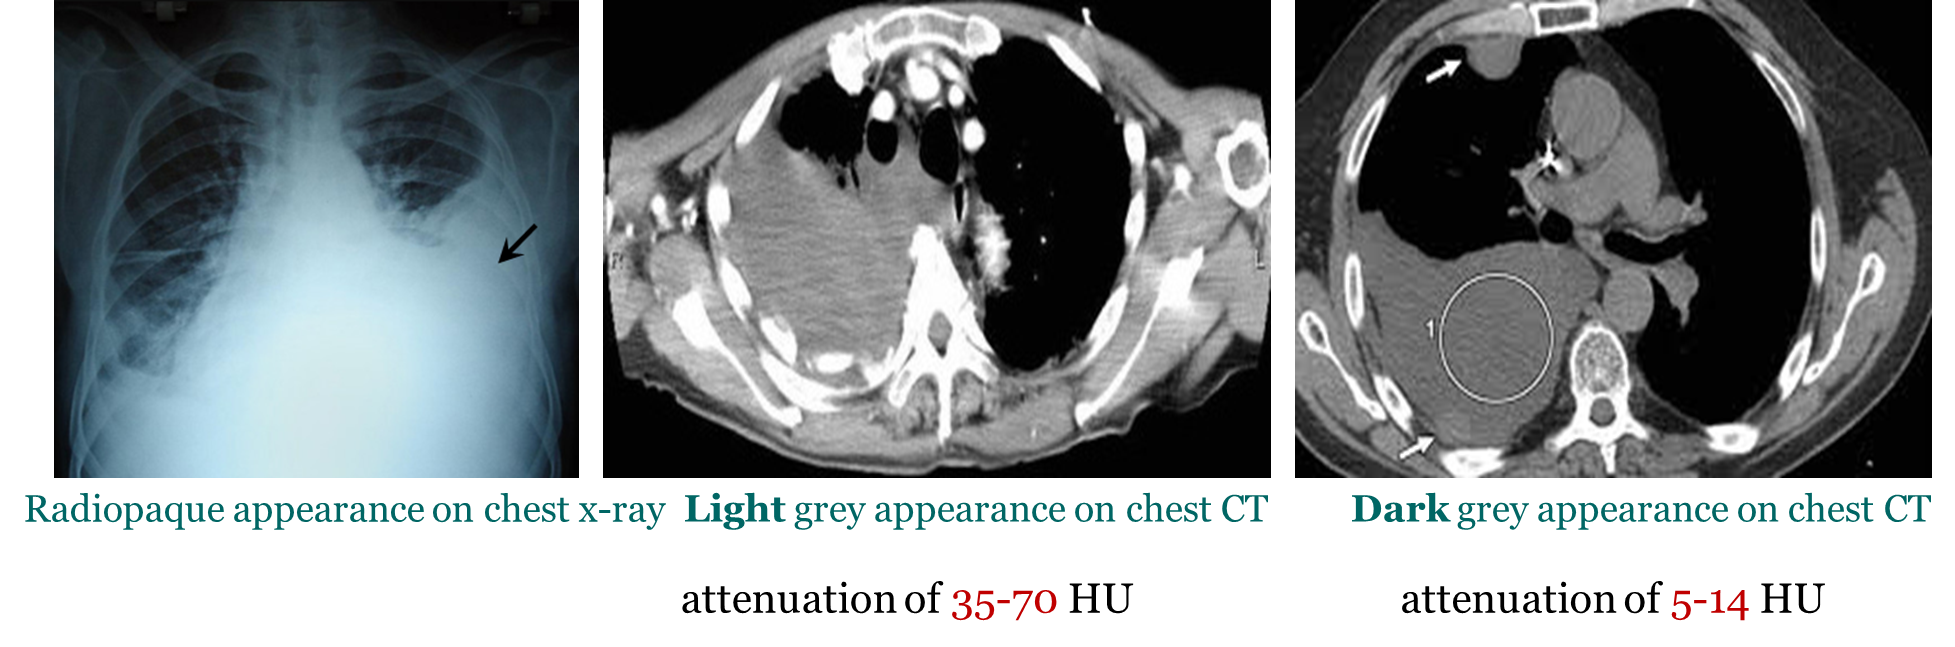

Hemothorax

_____ is a collection of the blood within the plural space (between visceral and parietal layers).

This pathology typically has an attenuation of 35-70 HU.

Pleural effusion typically has an attenuation of 5-14 HU.